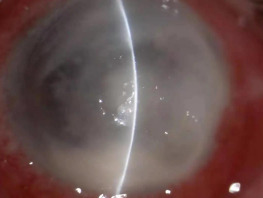

真菌性角膜炎是一種由致病真菌引起的、致盲率極高的感染性角膜病。常見的致病菌為曲霉菌,其次為鐮刀菌、白色念珠菌、頭芽胞菌及鏈絲菌等??沙霈F(xiàn)免疫環(huán)、衛(wèi)星灶、偽足、菌絲苔被、前方積膿及內(nèi)皮斑。